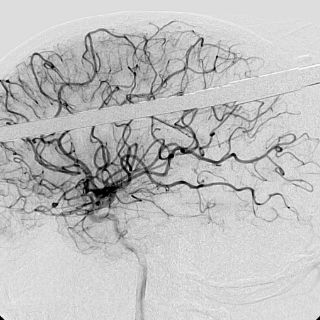

El especialista señaló que un infarto cerebral es producido por la interrupción del flujo sanguíneo debido a un coágulo isquémico o por la ruptura de un vaso dando lugar a un derrame hemorrágico.